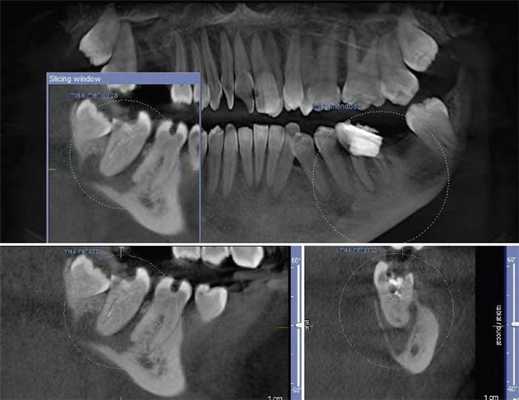

Фото 8. Подтверждение диагноза ИПКР на рентгенограмме.

Фото 9. Подтверждение диагноза на КТ-срезе.

Фото 10. Распространение ИПКТ в парапульпарном апикальном направлении (срез КЛКТ).

По причине принципов получения рентгенологических изображений, двухмерной природы рентгенограмм и значительного перекрытия нескольких анатомических образований, периапикальные снимки, или снимки по типу bitewing, часто не являются достаточно чувствительными для диагностики ИПКР. Также информативность данных методов при ИПКР часто связана с объемом потери твердых тканей зуба. Конусно-лучевая компьютерная томография (CBCT) является особенно полезной на ранних этапах регистрации очага поражения, хотя учитывая, что данный метод редко используется с целью скрининга, ИПКР снова-таки часто диагностируется как дополнительная находка при диагностике каких-то других заболеваний или при планировании комплексных алгоритмов лечения. Пародонтальная потеря костной ткани крайне редко отмечается в области внешней пришеечной резорбции.

При рентгенологической идентификации ИПКР чаще всего напоминает кариозный дефект V класса. При локализации поражений со щечной или язычной сторон из-за графического наложения на область пульпы зуба они могут вызывать некую размытость ее контура. По мере развития патологии она прогрессируют к пульповой камере, не вызывая прямого воздействия на пульпу. В большинстве случаев, даже среди обширных поражений, твердые ткани, окружающие пульпу, часто выглядят почти неповрежденными, что на рентгенограмме проявляется в форме тонкой рентгеноконтрастной линии между дефектом ИПКР и пульпой зуба.